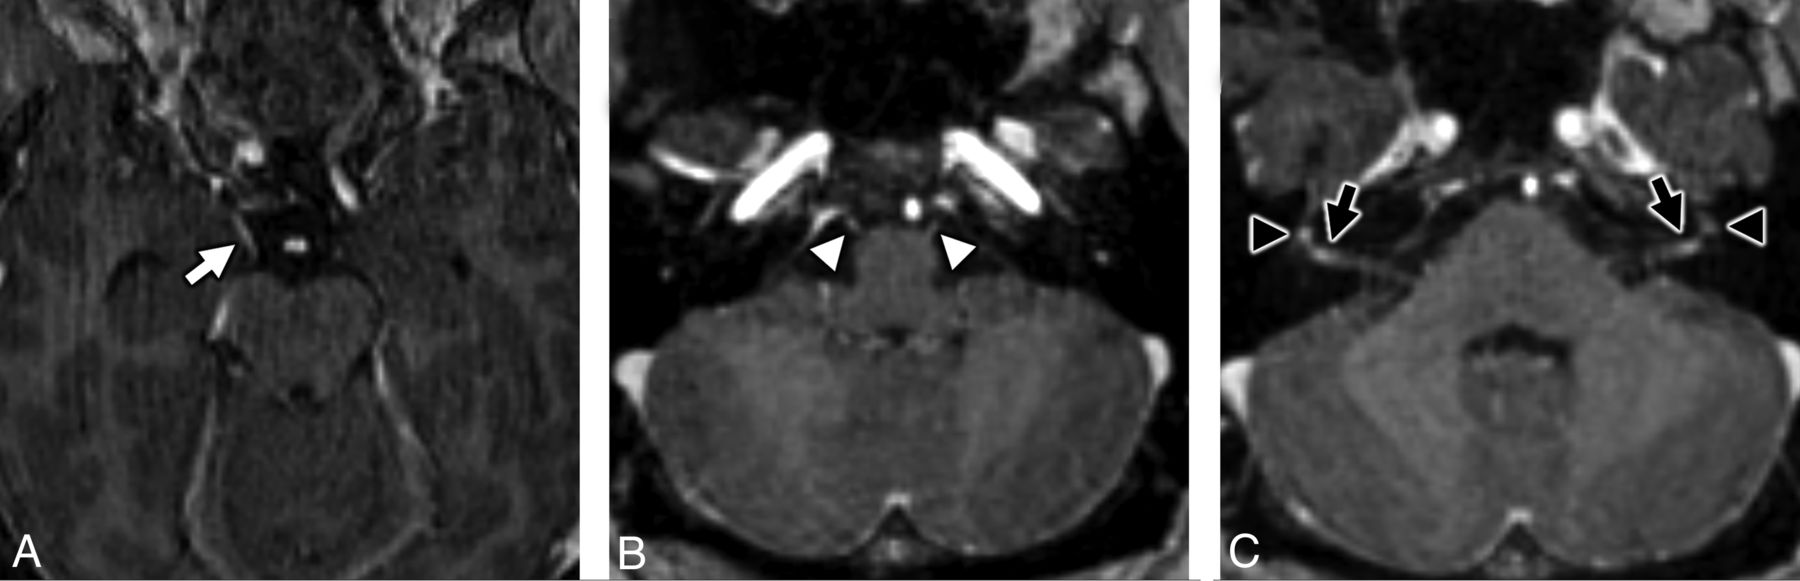

MR imaging of the temporal bones in a patient with antecedent COVID-19 and new-onset bifacial weakness and paresthesia subtype Guillain-Barré syndrome. Axial postcontrast T1-weighted fat-saturated MR imaging of the temporal bones (A) shows subtle-but-abnormal enhancement along the cisternal segments of the abducens nerves (CNVI) bilaterally (white arrows), as well as subtle enhancement along the tympanic segments of the intratemporal facial nerves (CNVII) bilaterally (white arrowheads). Coronal postcontrast T1-weighted fat-saturated MR imaging (B) shows subtle asymmetric enhancement along the cisternal segment of the right oculomotor nerve (CNIII, black arrow).

MRI of the brain in a patient with antecedent COVID-19 and new onset bifacial weakness and paresthesias subtype Guillain-Barré syndrome. Axial post-contrast T1-weighted SPoiled Gradient-Recalled (SPGR) MRI shows abnormal enhancement of the right oculomotor nerve (CNIII, white arrow, A), the cisternal segments of the abducens nerves (CNVI) bilaterally (white arrowheads, B), the distal canalicular segments of the facial nerves (CNVII) bilaterally (black arrows, C), and the proximal tympanic segments of the intratemporal facial nerves (CNVII) bilaterally (black arrowheads, C).